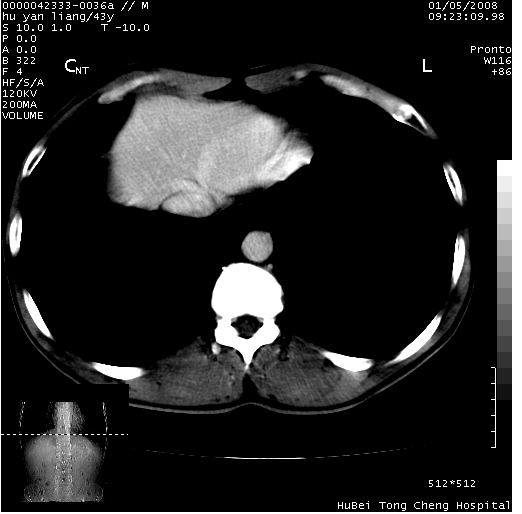

患者 男,43岁。右上腹不适1年余。既往有“肝右叶肝脓肿”病史,经保守治疗后痊愈。

上中腹部ct轴位平扫+增强扫描(层厚10mm,螺距1.0,重建间隔10mm),图像如下:

肝右上叶偏后方较大团片状钙化灶,支持:肝脓肿后遗改变!

肝右叶后段团块状钙化灶,结合病史考虑肝脓肿痊愈后表现。